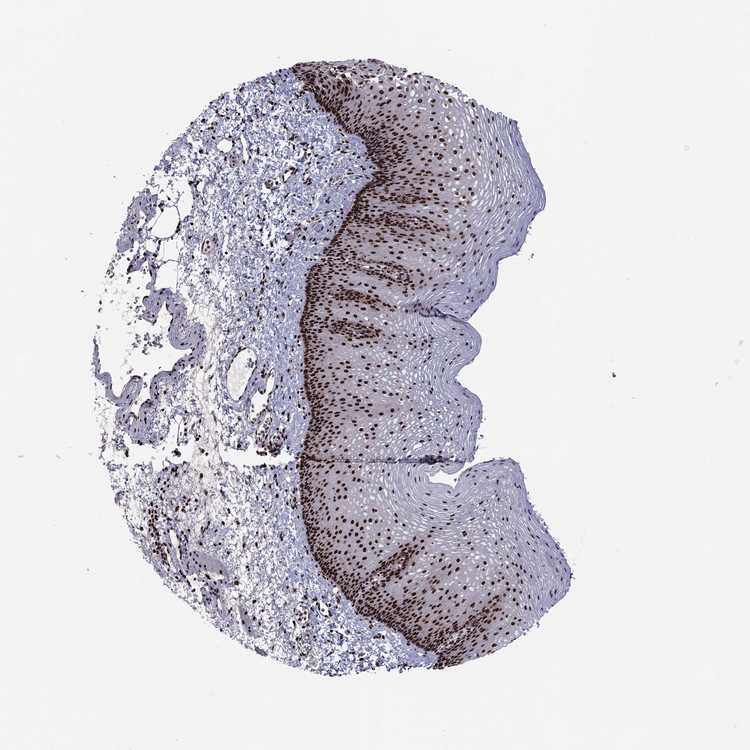

ESOPHAGUS - Antibody stainingi

Antibody staining in the annotated cell types in the current human tissue is reported as not detected, low, medium, or high, based on conventional immunohistochemistry profiling in selected tissues. This score is based on the combination of the staining intensity and fraction of stained cells.

Each image is clickable and will lead to virtual microscopy that enables deeper exploration of all samples and also displays staining intensity scores, fraction scores and subcellular localization as well as patient and tissue information for each sample.

Antibody HPA063665

Squamous epithelial cells High